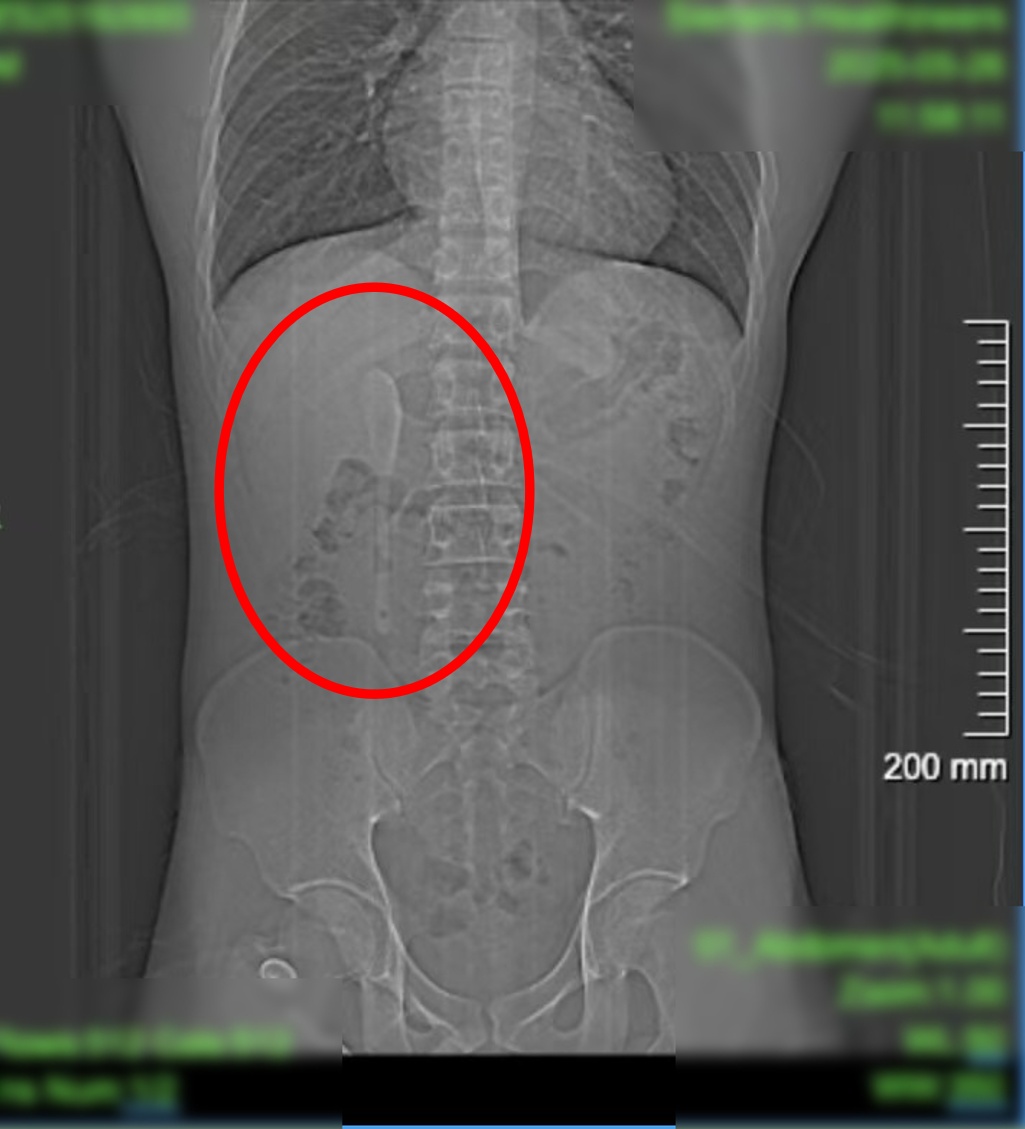

CT显示,这支近15厘米长勺状物体,严丝合缝地横亘于十二指肠球部与降部交界的生理狭窄处,稍有不慎即可能刺穿肠壁,引发腹膜炎或大出血。

昨天(6月18日)下午,小言被推进内镜手术室。虽然医护团队对手术难度有所预判,但内镜画面仍让团队倒吸凉气——勺子的“头”卡在十二指肠球部,而它的“长柄”则一路延伸下去,拐了个弯卡在了更深的十二指肠降部与水平部交界处。